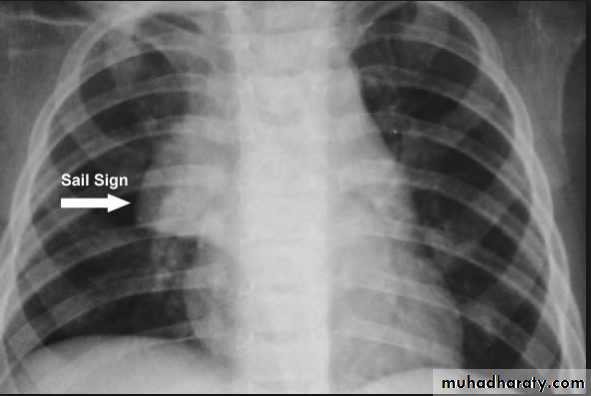

Tension pneumothorax.

On a posteroanterior chest x-ray (A), the left hemithorax is very dark or lucent because the left lung has collapsed completely (white arrows).

The tension pneumothorax can be identified because the mediastinal contents, including the heart, are shifted toward the right, and the left hemidiaphragm is flattened and depressed. A computed tomography scan done on a different patient with a tension pneumothorax (B) shows a completely collapsed right lung (arrows) and shift of the mediastinal contents to the left.